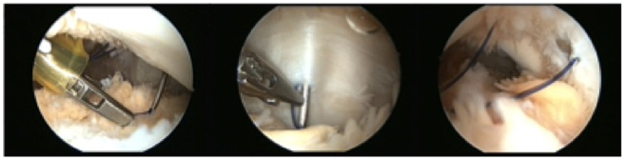

After failed conservative treatment the patient was submitted to an arthroscopic all inside medial patellar plication (Figure 4 & 5). This technique was made with two standard lateral and medial portals and one accessory superolateral portal; we placed a working cannula in this portal. Standard diagnosis arthroscopy was made and then with leg in extension the patellofemoral compartment was approached. There was synovitis, type 2 patellar cartilage lesions and maltracking of the patella was observated. A partial synovectomy and debridment of cartilage lesions with shaver blade was made and then we did the arthroscopic medial plication with lateral retinaculum release. The medial retinaculum became tense and the patella was aligned in the trochlear groove, with lateral translation inferior to 50%.

Figure 4 Intra operative arthroscopic images showing the suture limbs being passed in the medial retinaculum over the Tuohy needle, and the final aspect before knot tying, after the synovial abrasion between suture limbs

Figure 5 Intra operative arthroscopic images showing knot tying and the final image after the medial retinaculum plication.